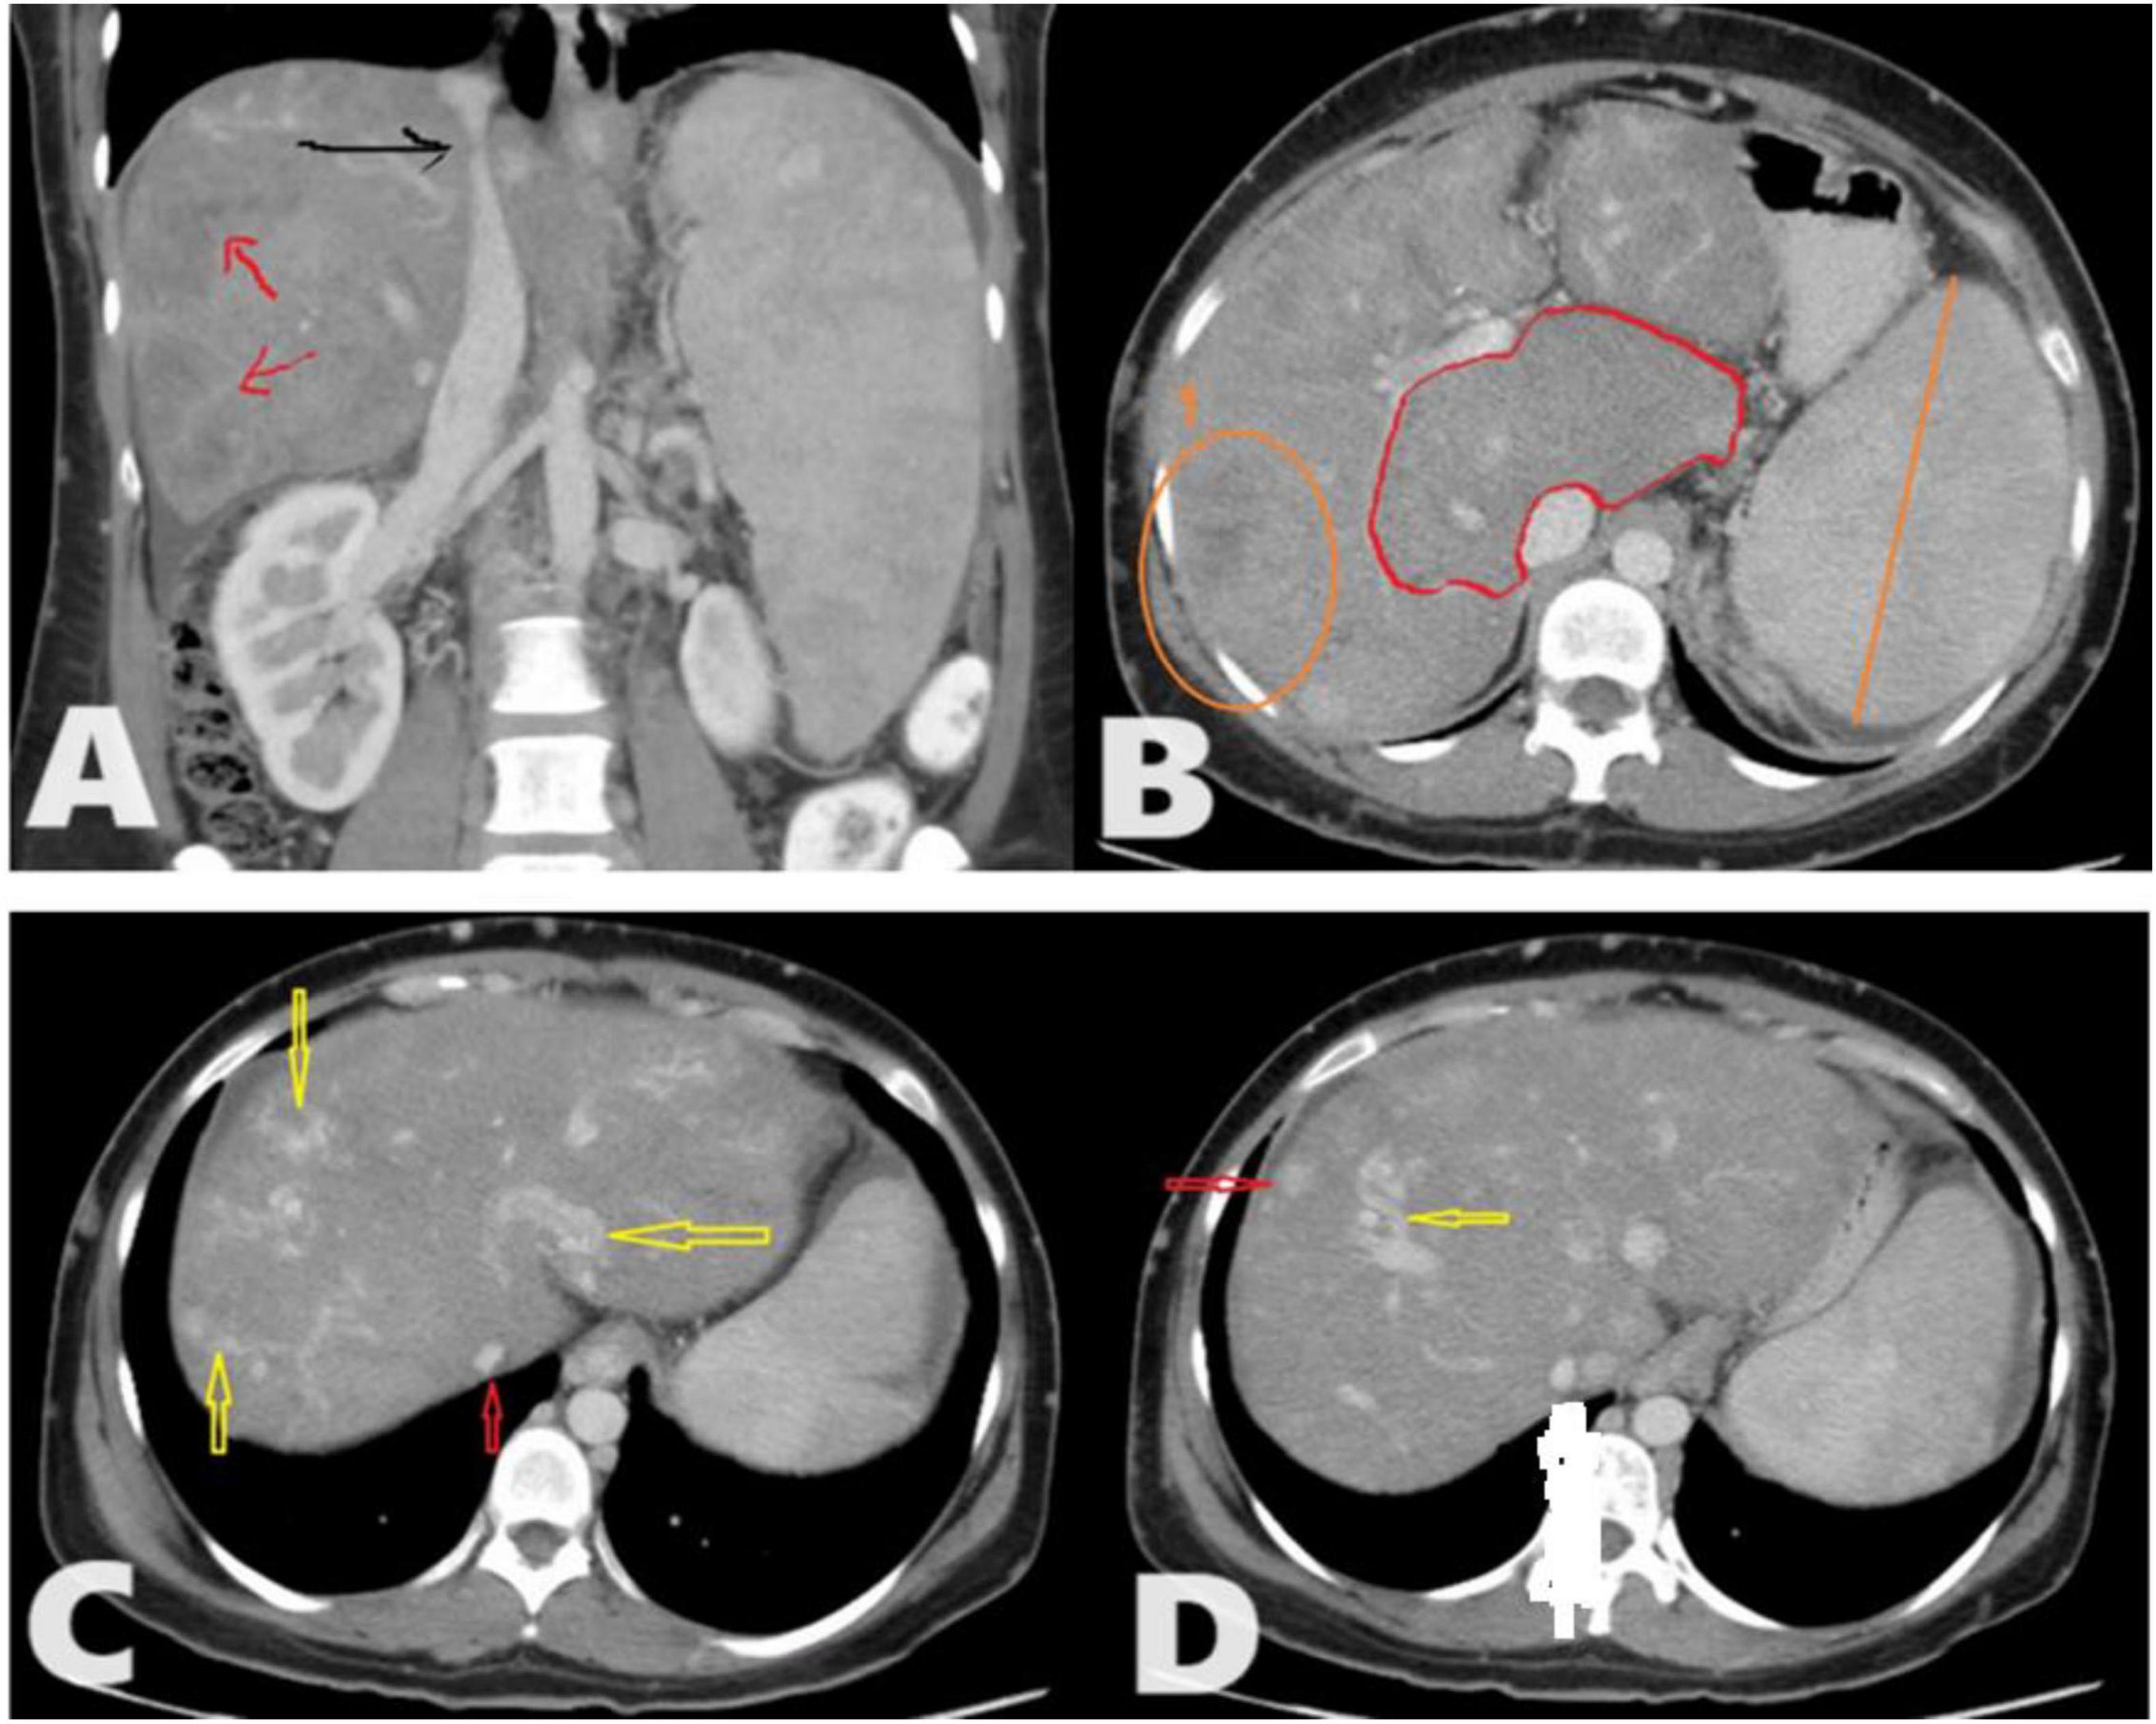

Figure 1. A total of 35 years female presented to the radiology department with chronic abdominal pain. Triphasic computed tomography (CT) abdomen reveals; (A) Chronic Budd-Chiari syndrome (BCS) manifested as Enlarged liver with heterogeneous enhancement and a patchy hepatogram with areas of hypoperfusion (Red arrows). The hepatic part of inferior vena cava (IVC) shows a focal stenosis which may indicate the presence of an IVC web (Black arrow). (B) The caudate lobe is disproportionately enlarged compared to the rest of the liver. No IVC/portal vein thrombosis. (C) There are multiple intrahepatic collateral vessels, some of which drain directly into the IVC (yellow arrows) and narrow IVC (red arrow) with no enhancement of the hepatic veins (HVs) (inability to identify HVs). (D) There are multiple enhancing nodules spread throughout the liver (Red arrow) as an example.

Digital Subtraction Angiography (DSA) is considered a “gold standard” modality to diagnose BCS, but its invasive procedure involving the use of contrast materials and ionizing radiation (42), Doppler US is considered the first modality of choice for initial investigation when BCS is suspected (43), but it highly depends on the operator’s experiences; ultrasound is also affected by excessive ascites and bowel gases (42, 44). CT is widely used in BCS diagnosis, it’s used to evaluate liver parenchyma, HVs, IVC, and venous collaterals (45). However, CT is considered less accurate in the detection of venous abnormalities compared with CDUS and MRI (12). Also, the use of contrast agents may lead to allergic reactions, and possibilities of contrast-induced nephrotoxicity were the major drawbacks (46). MRA is an alternative technology used for vascular assessment in BCS without the use of contrast materials (47). It is also used for the classification of BCS patients (48). A high rate of heartbeats, massive ascites, and uneven breathing were factors of misdiagnosis in MRA of BCS patients (42). The sensitivities and specificities for Doppler in the diagnosis of BCS were 89% and 68%, 89% and 72% for CT, and 93% and 55% for MRI, respectively, indicating higher MRI sensitivity and higher CT specificity compared to both modalities. MRI yielded an AUC of 90.8% compared with 88.4% for CT and 86.6% for Doppler ultrasound (49). This research was conducted to characterize and identify the common feature of Budd Chiari syndrome in the Sudanese population using CT scan, CT and Doppler US are the available and most used diagnostic modalities in Sudan to identify the BCS features, contrast-enhanced liver CT is readily used for abdominal and liver disease scans more frequently than MRI, due to the limited number of MRIs in Sudan. Figures 1, 2 give a clear picture of BCS features and their related complications. Different age groups were investigated; in which BCS affects both children and adults, a median age of 10.5 (2–16 years) was identified (50) which is commonly associated with abdominal distention in more than 86% of children and upper GI bleeding in more than 36% of patients as common primary indication and findings as detected by Ultrasound and MRI in few patients. BCS is rare in children and accounts for more than 16 percent of pediatric liver illnesses in Asia, but less than 0.1 percent in Western nations (51), our present research indicates that the most common age group for affected children was 02–14 years, same results also indicated by different authors including (50, 52). This study focused on different ages as adults were more frequently included resulting from a random collection of data, a common age group affected in adult patients at the time of diagnosis was 39–52 years, as also seen by Ollivier-Hourmand et al. (53) in France, who stated the mean age was 40 ± 14 years. A total of 45 years mean age as in (54). BCS affects both males and females, but in this study, the most affected gender was male at 57.4%, while females represented 42.6% of the total sample distribution. This result is quite different from a variety of studies reported by different authors, as females were commonly affected rather than male gender, as in (55, 56), Female predominance is reported in the West (67%) (57). But also, slight male predominance was reported in India (58) and Japan (59). Dilawari et al. (58) stated that males are commonly associated with IVC obstruction, while females are commonly associated with Hepatic Viens (HV) obstructions. Manifestation of such clinical signs depends on the degree of hepatic vein involvement and portal vein, as in Figure 1A. This study showed that the most common signs and manifestations of BCS were abdominal pain seen in 57.4% of patients, followed by jaundice associated with edema and/or vomiting in 42% of patients. Less frequent signs were seen as abdominal distention as a result of intra-abdominal bleeding in 1.63% of the study populations. Different authors report that hepatomegaly, ascites, abdominal discomfort, and the existence of dilated superficial abdominal wall veins are the main characteristics of BCS (13, 60). To distinguish between vascular and parenchymal liver disease was commonly diagnosed using contrast-enhanced CT abdomen with varying contrast timing. Computed tomography has recently been shown to be an excellent modality of choice for the characterization, classification, and staging of BCS, especially for chronic stages of disease (13). The liver parenchymal appearance showed various patterns of enhancement, with a heterogenous (nutmeg) liver seen in most of the patients 27.87%. In comparison, an enlarged liver also with heterogeneous contrast enhancement was identified in more than 24% of the CT scan results. Liver cirrhosis is a remarkable characteristic of different chronic liver diseases, especially hematogenous-associated diseases. BCS is a rare cause of liver cirrhosis that can be distinguished from other causes of cirrhotic disease by normal values of liver function and prominent portal hypertension (PH) (61). Cirrhosis caused by BCS seen shows 14.8% of patients with cirrhotic heterogeneous liver, as in Table 1. As we previously mentioned, causes of BCS are most commonly due to vascular causes, HV thrombosis due to hemodynamic disorders, or secondary due to tumor thrombus from RCC or HCC (1, 9, 10). Hepatic vein thrombosis was seen in 11 patients (18.03%), A CT scan of the patient with BCS reveals a wide range of findings including biliary diseases, hepatic lesions either benign or malignant lesions, chronic liver diseases such as viral or non-viral conditions, gallbladder stone associated with wall thickening seen in 6.56% of BCS patients, also the background of the shrunken liver with an irregular outline in 4.92%, liver cyst or gallbladder cancer, IVC thrombosis associated with hemangioma, chronic hematological disease, hepatic vein obstruction with tumoral thrombus in IVC, chronic liver disease associated with multiple nodules, and chronic hepatic vein thrombosis as presented in Table 2. Collectively these (CT findings) related to BCS were seen in more than 52% of study populations compared to more than 87% of patients, as reported by Denninger et al. (9); see Table 2. In 80%–91% of instances, the caudate lobe enlarges as a result of distinct venous outflow (62, 63). A “flip-flop” pattern develops during the portal venous phase, with modest attenuation of the liver’s core region due to washout. A different form of venous changes and appearance in computed tomography were identified in this study. HVs were not identified in more than half of the patients diagnosed with BCS (55.73%), narrowing or barely seen hepatic veins, slit-like (compressed) IVC, portal dilatation, dilated celiac, and SM vein; all these changes were seen in Sudanese populations, as presented in Table 3. BCS is linked to varying degrees of variceal alterations because of venous involvement. Commonly, no variceal changes are seen with BCS in a significant percentage of the patients including more than 59% of them, but due to these obstructive changes and increased vascular permeability. The most common site of varices is the lienorenal and gastro-esophageal region seen in 37.7% of patients with BCS and varying degrees of involvement in gastric and esophageal veins. Still, many cases were not associated with varices in more than 59% of patients, see Table 4. Naganuma et al. (64) reported that; BCS is one of the main causes of intrahepatic and abdominal collaterals. Hepatomegaly and ascites are caused by acute blockage of the hepatic venous outflow (attenuation/thrombosis of HVs and/or IVC). Venous thrombosis causes the portal venous blood influx to be delayed or reversed as well as an increase in sinusoidal pressure. In the acute form, hepatic necrosis happens quickly, and venous collaterals have not yet formed (13, 63). This study reported that more than 73.7% of patients presented with ascites (associated with an umbilical hernia in 1.63%) of the patients. In addition to other rare complications such as compressed duodenum, splenic, and SM vein occlusion, as shown in Table 1. Ascites is commonly associated with older ages, especially 39–52 years as the peak age of patients is strongly linked to such complications. Radiologic investigations of BCS are non-invasive procedures. US allows the assessment of hepatic venous flow and heterogeneity, while CT and MRI can depict HVs thrombosis and IVC occlusion or compression.